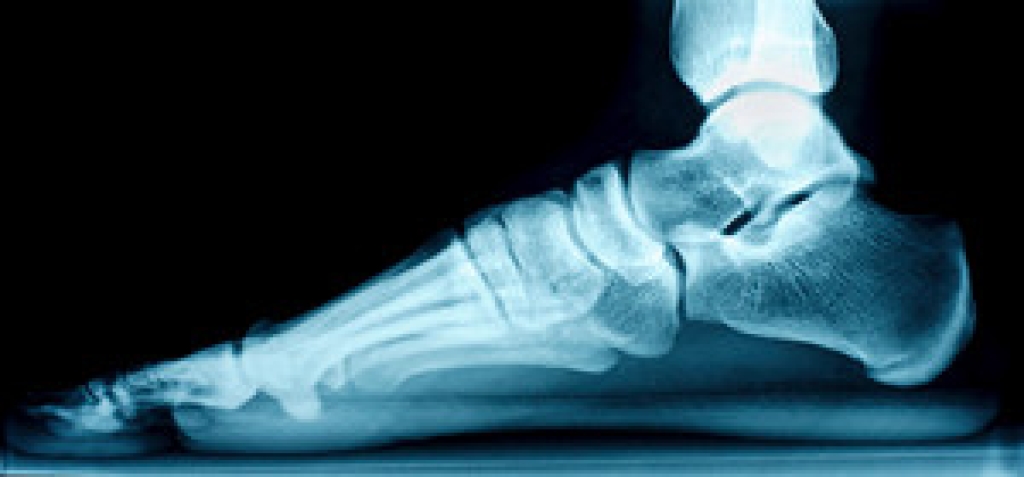

Neuropathy is a condition that leads to damage to the nerves in the body. Peripheral neuropathy, or neuropathy that affects your peripheral nervous system, usually occurs in the feet. Neuropathy can be triggered by a number of different causes. Such causes include diabetes, infections, cancers, disorders, and toxic substances.

To treat neuropathy in the foot, podiatrists will first diagnose the cause of the neuropathy. Figuring out the underlying cause of the neuropathy will allow the podiatrist to prescribe the best treatment, whether it be caused by diabetes, toxic substance exposure, infection, etc. If the nerve has not died, then it’s possible that sensation may be able to return to the foot.